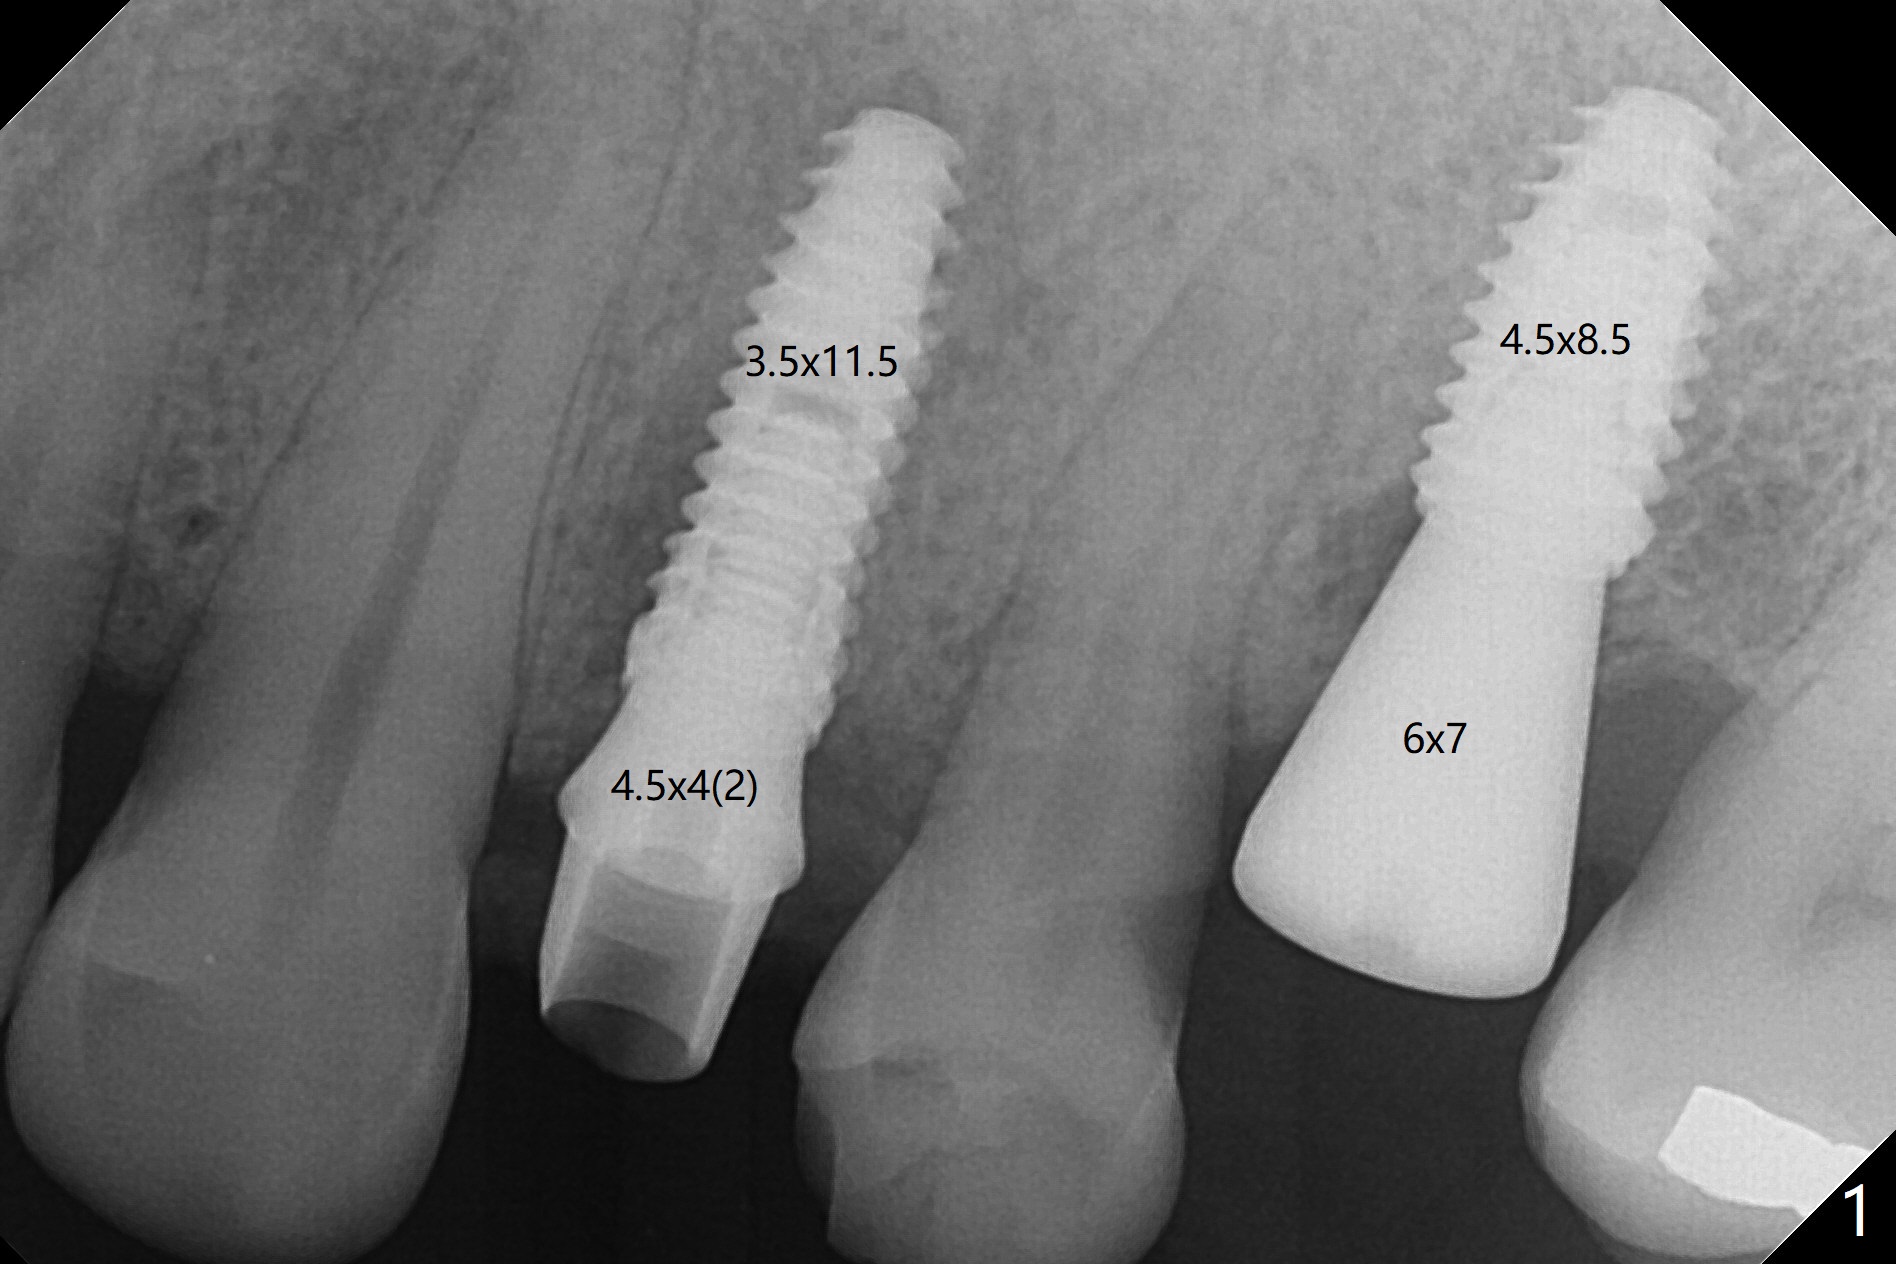

To remove the subgingival residual root of the tooth #12, buccal flap is raised, which provides access to see thread formation in the coronal portion of the socket following use of cortical tap. Bone harvested from osteotomy is placed in the remaining buccal socket (Fig.1). Bone density is so high at #21 that 4.5x8.5 and 4.5x10 mm drills are used before placement of a 4.5x10 mm with 12 mm offset in addition to use of cortical tap and back up of the implant several times (Fig.2).